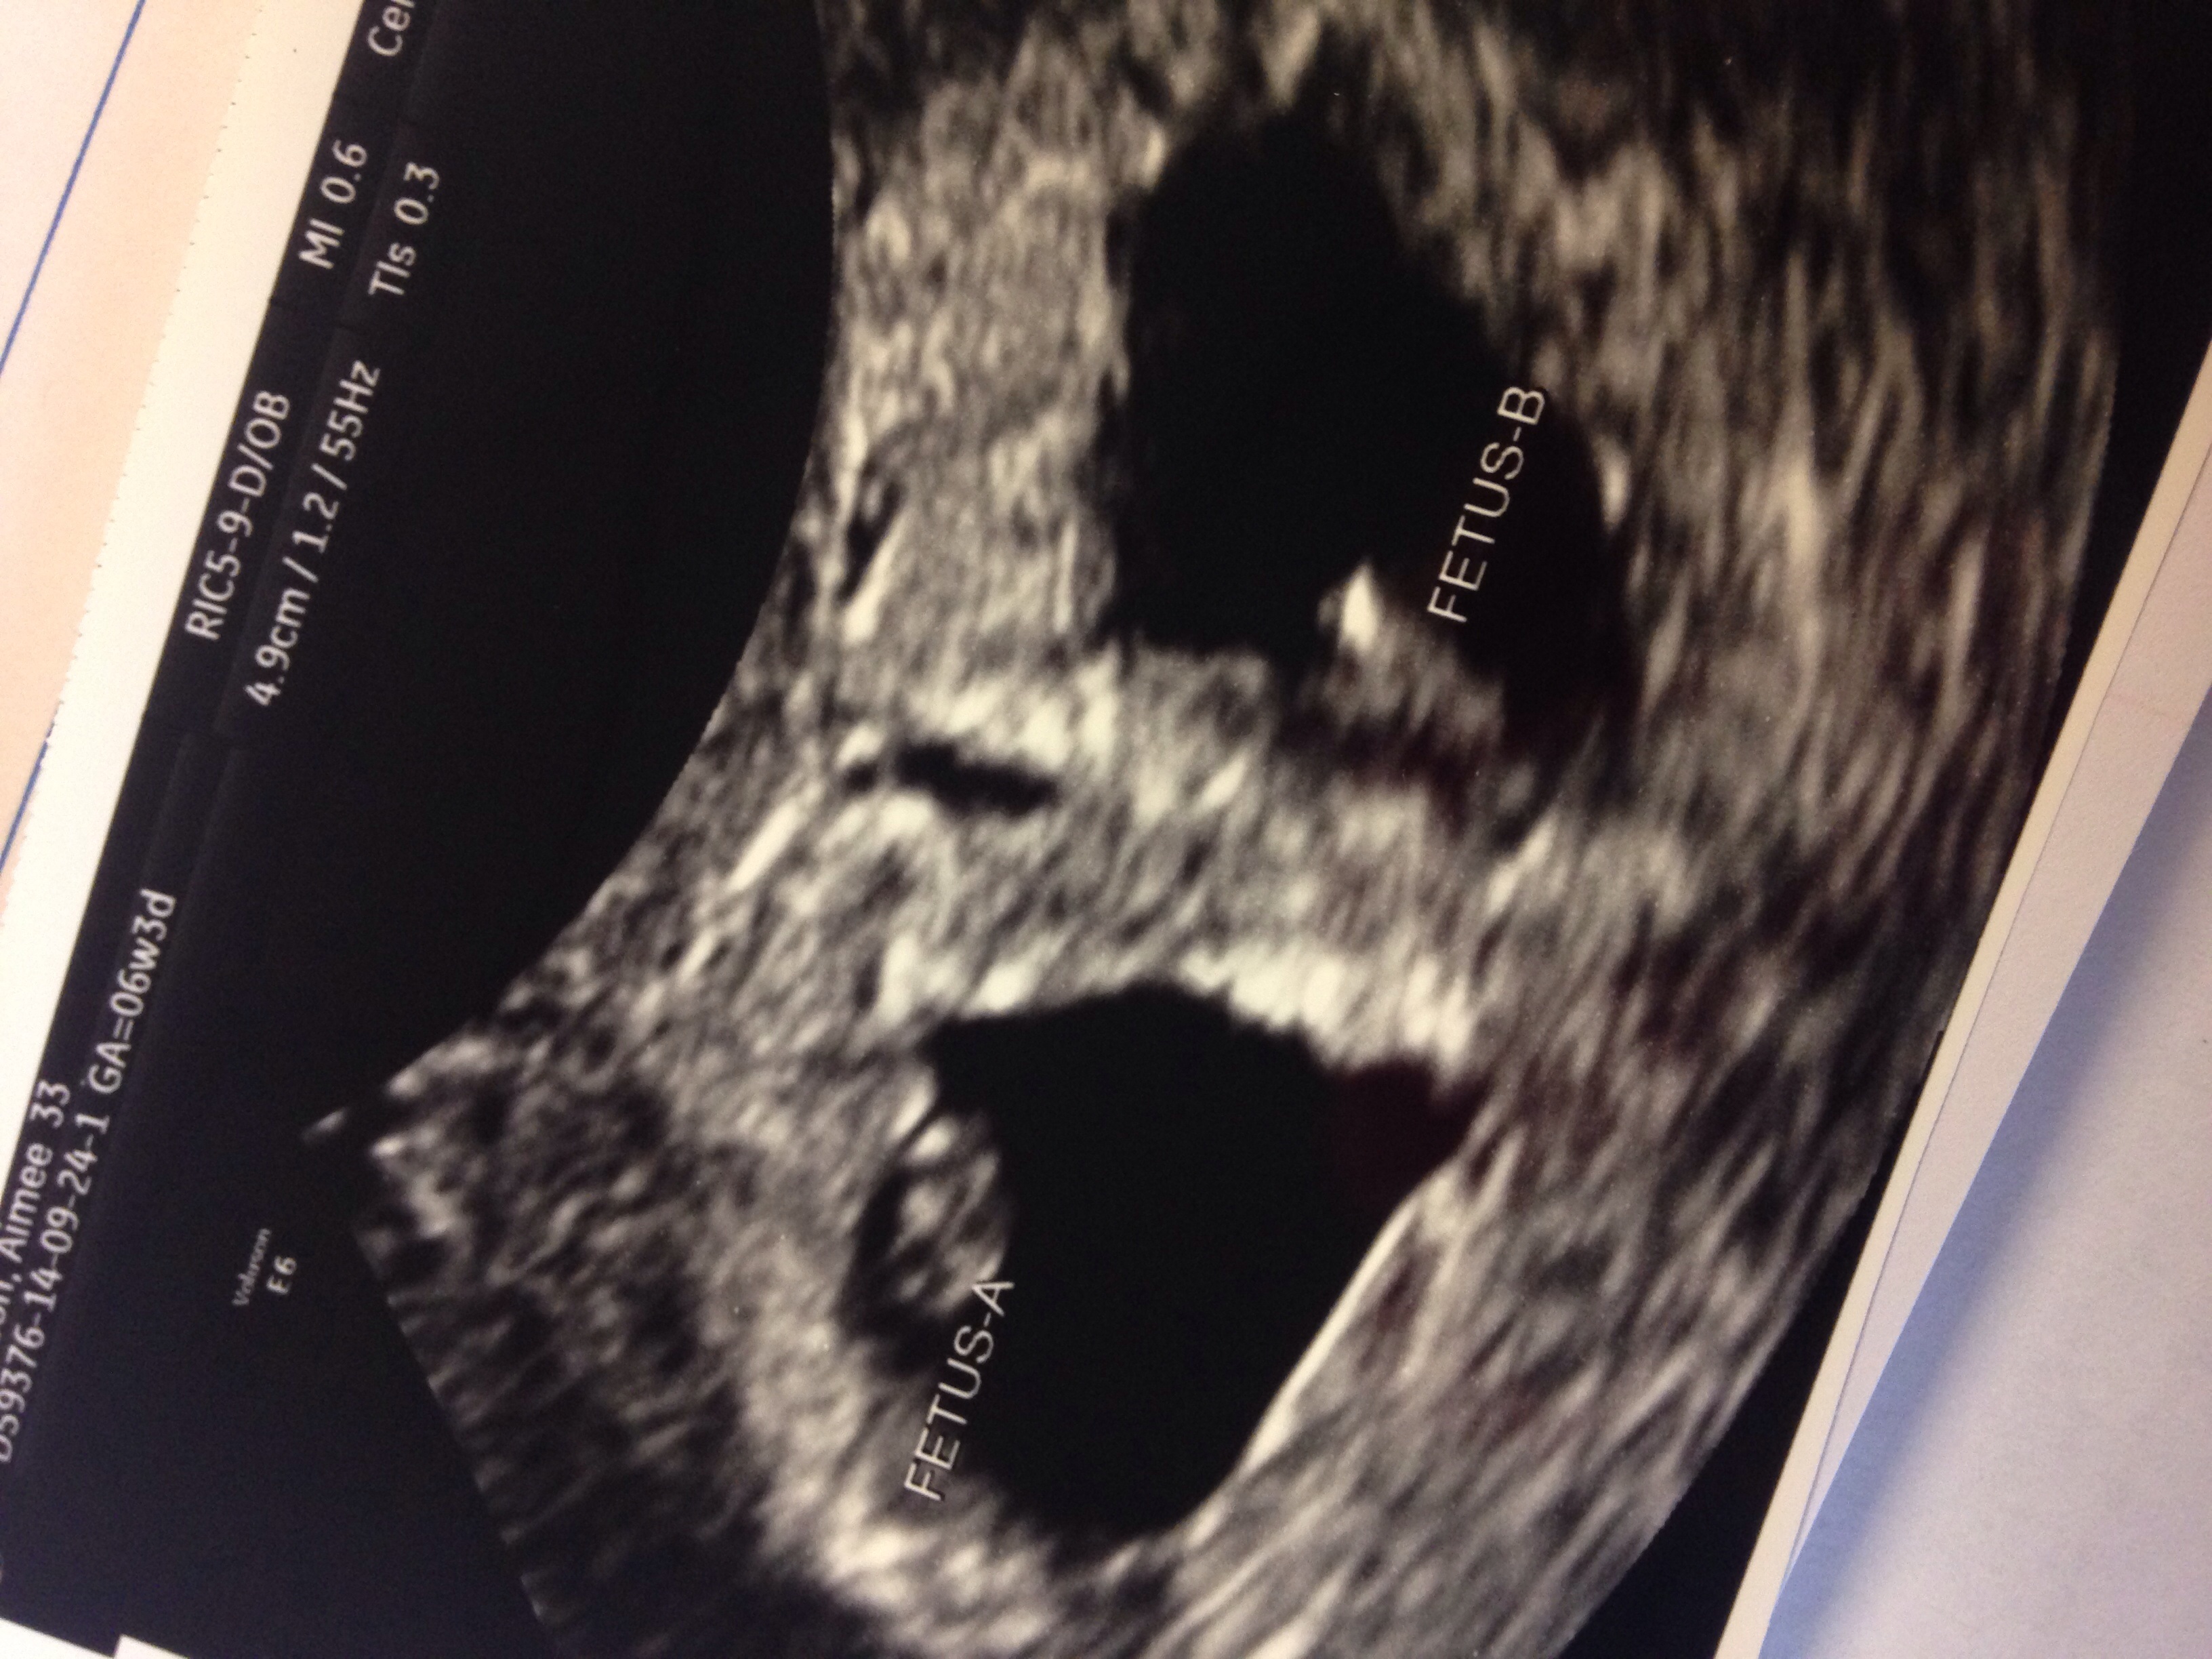

We've got two heartbeats!! PR

Ahhhhhh!!!

All further updates will be on GPM. BUT IM NOT LEAVING.

Baby Boy born 5.3.15